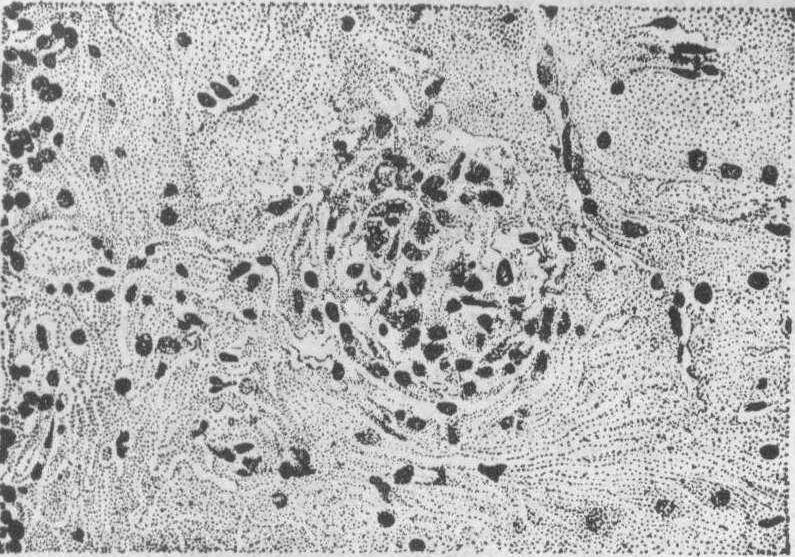

斑疹伤寒小结 立克次体进入人体后主要在血管内皮细胞内繁殖,所以小血管内皮细胞常肿胀增生,甚至阻塞管腔(血管炎),其外并有淋巴细胞等围绕。斑疹伤寒小结就是以增生的细小动脉或毛细血管为中心形成的。结节小,镜检才能看到。分布于大、小脑各处,尤其多见于大脑导水管周围,以及桥脑、延髓橄榄核等处的灰质。在皮肤、睾丸、心肌间质亦可发生,但不如脑内的小结多而明显。脑内的小结中央,毛细血管因内皮细胞肿胀增生常致管腔闭塞,周围有多数的小胶质细胞、小突胶质细胞及巨噬细胞等成分。脑内的这些小结是本病较为特殊的病变,在虱型斑疹伤寒中较蚤型中多见。

图1 脑的斑疹伤寒小结